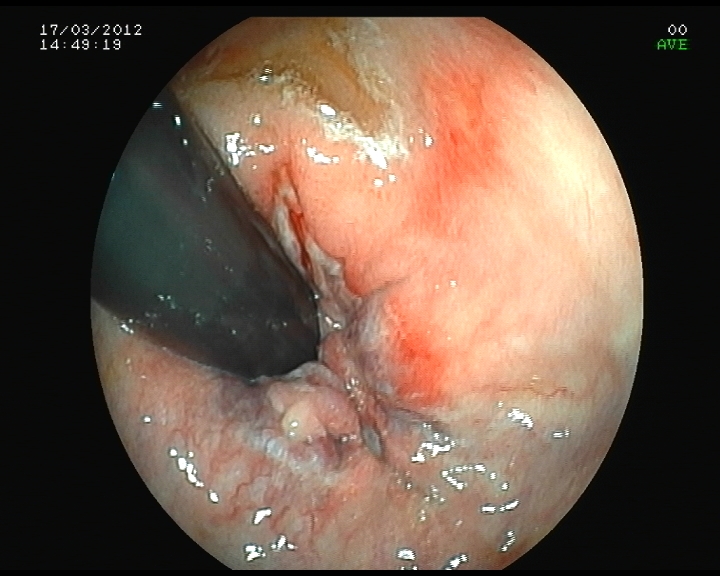

Dilatación de estenosis